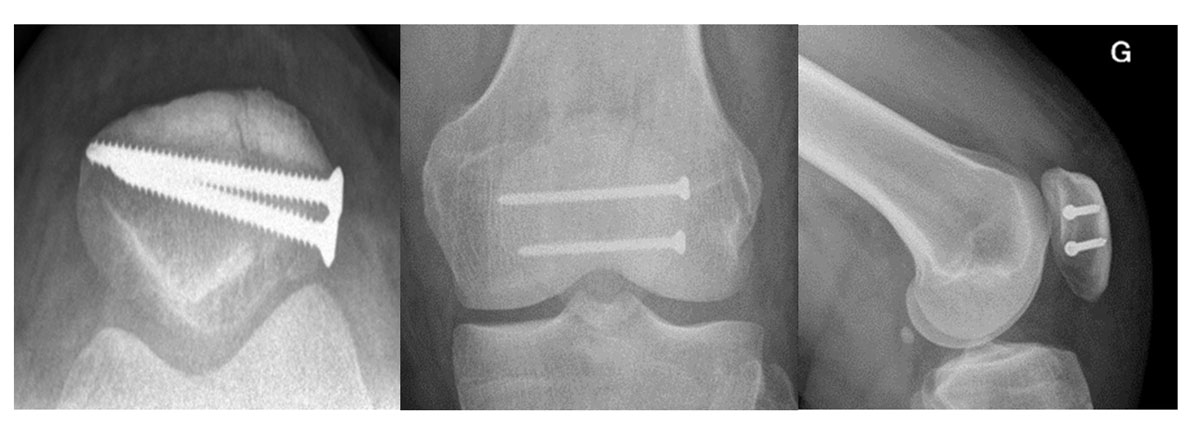

Based on the AO principle of anatomical reduction and compression, the screws must hold firmly in the bone, but the cancellous bone of the patella is not always a favourable site in cases of comminution and/or osteoporosis. Nonetheless, this technique has the advantage of reducing by 50% the rate of hardware removal (fig. 6) [22].

Figure 6 X-ray of knees with two screws for a longitudinal (vertical) fracture (CHUV.